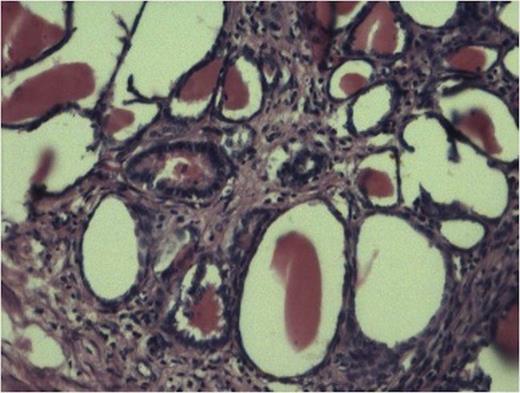

Gross examination of the specimen showed a multi-cystic sac-like structure measuring 11 x 6 x 2.5 cm along with the attached ureter. There was no visible renal tissue macroscopically. Cut surface of specimen showed multiple loculi with varied appearance and thinned out wall at some places with intervening thickened areas at others (Fig 1).

Tubules showing thyroidisation favouring chronic pylonephritis. (100x H and E stain).